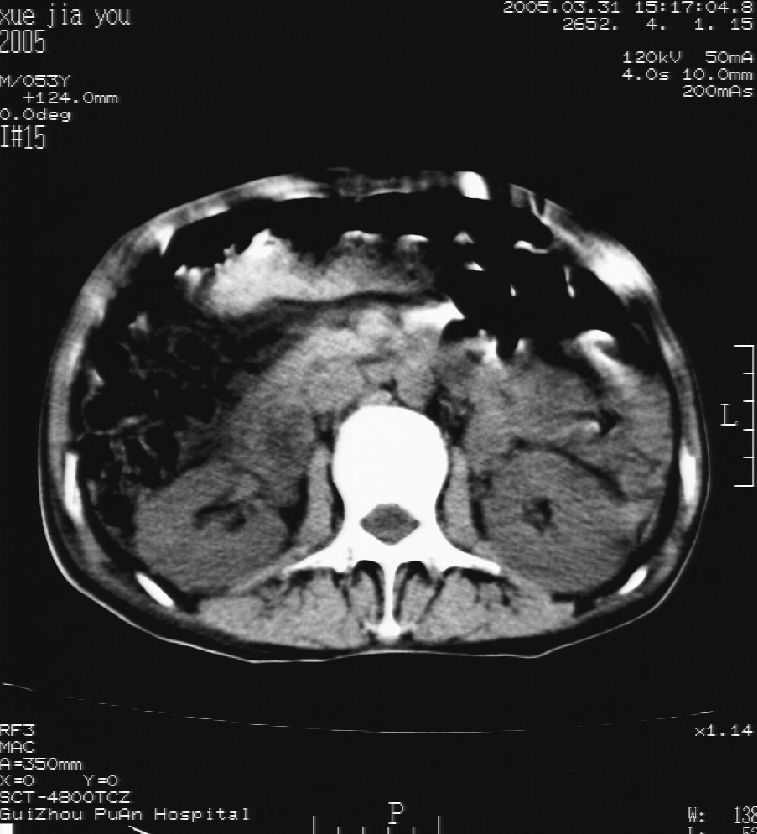

男 55岁  反复上腹痛1年,伴恶心呕吐。2005年做第一次检查后,到外院做b超检查提示肝囊肿,未做任何手术。2006年做过胆总管结石术。骨窗未见异常

这个病灶很有意思,怎么可能没有了呢?我考虑当时很可能是肝脏脓肿(b超示囊肿是有可能误诊的,因为影像表现都是低回声吗?),现在脓肿吸收了,肝脏萎缩,肝裂增宽了.别的肝叶代偿增大,不过现在左内叶的确有个占位,肝内多发结石,脾脏比以前大,不排除有肝硬化可能.建议增强扫描给于定性!!!!

肝硬化\\脾大,肝左叶肝癌可能性大,建议增强扫描.肝内胆管多发性结石.

1, 肝硬化,脾大;2,肝左叶肝癌可能性大,建议增强扫描.3,肝内胆管多发性结石.

考虑肝内胆管多发结石引起的肝内局部炎症,这样可以解释2005年肝右叶病灶的吸收和左叶新病灶.

肝硬化、脾大、肝内胆管多发结石。肝左叶低密度占位。建议增强扫描.排除肝癌